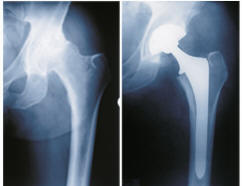

People should be aware that according to the information posted Smith and Nephew’s (Birmingham Hip ) BHR has cobalt and chromium components.

SMITH & NEPHEW reports that complication rates and types of complications are similar to other hip replacement procedures. (Birmingham Hip Resurfacing system risks and patient information guide).